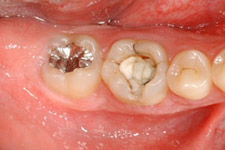

治療前

治療前の様子。第一大臼歯が割れてしまっていて治療することが困難です。